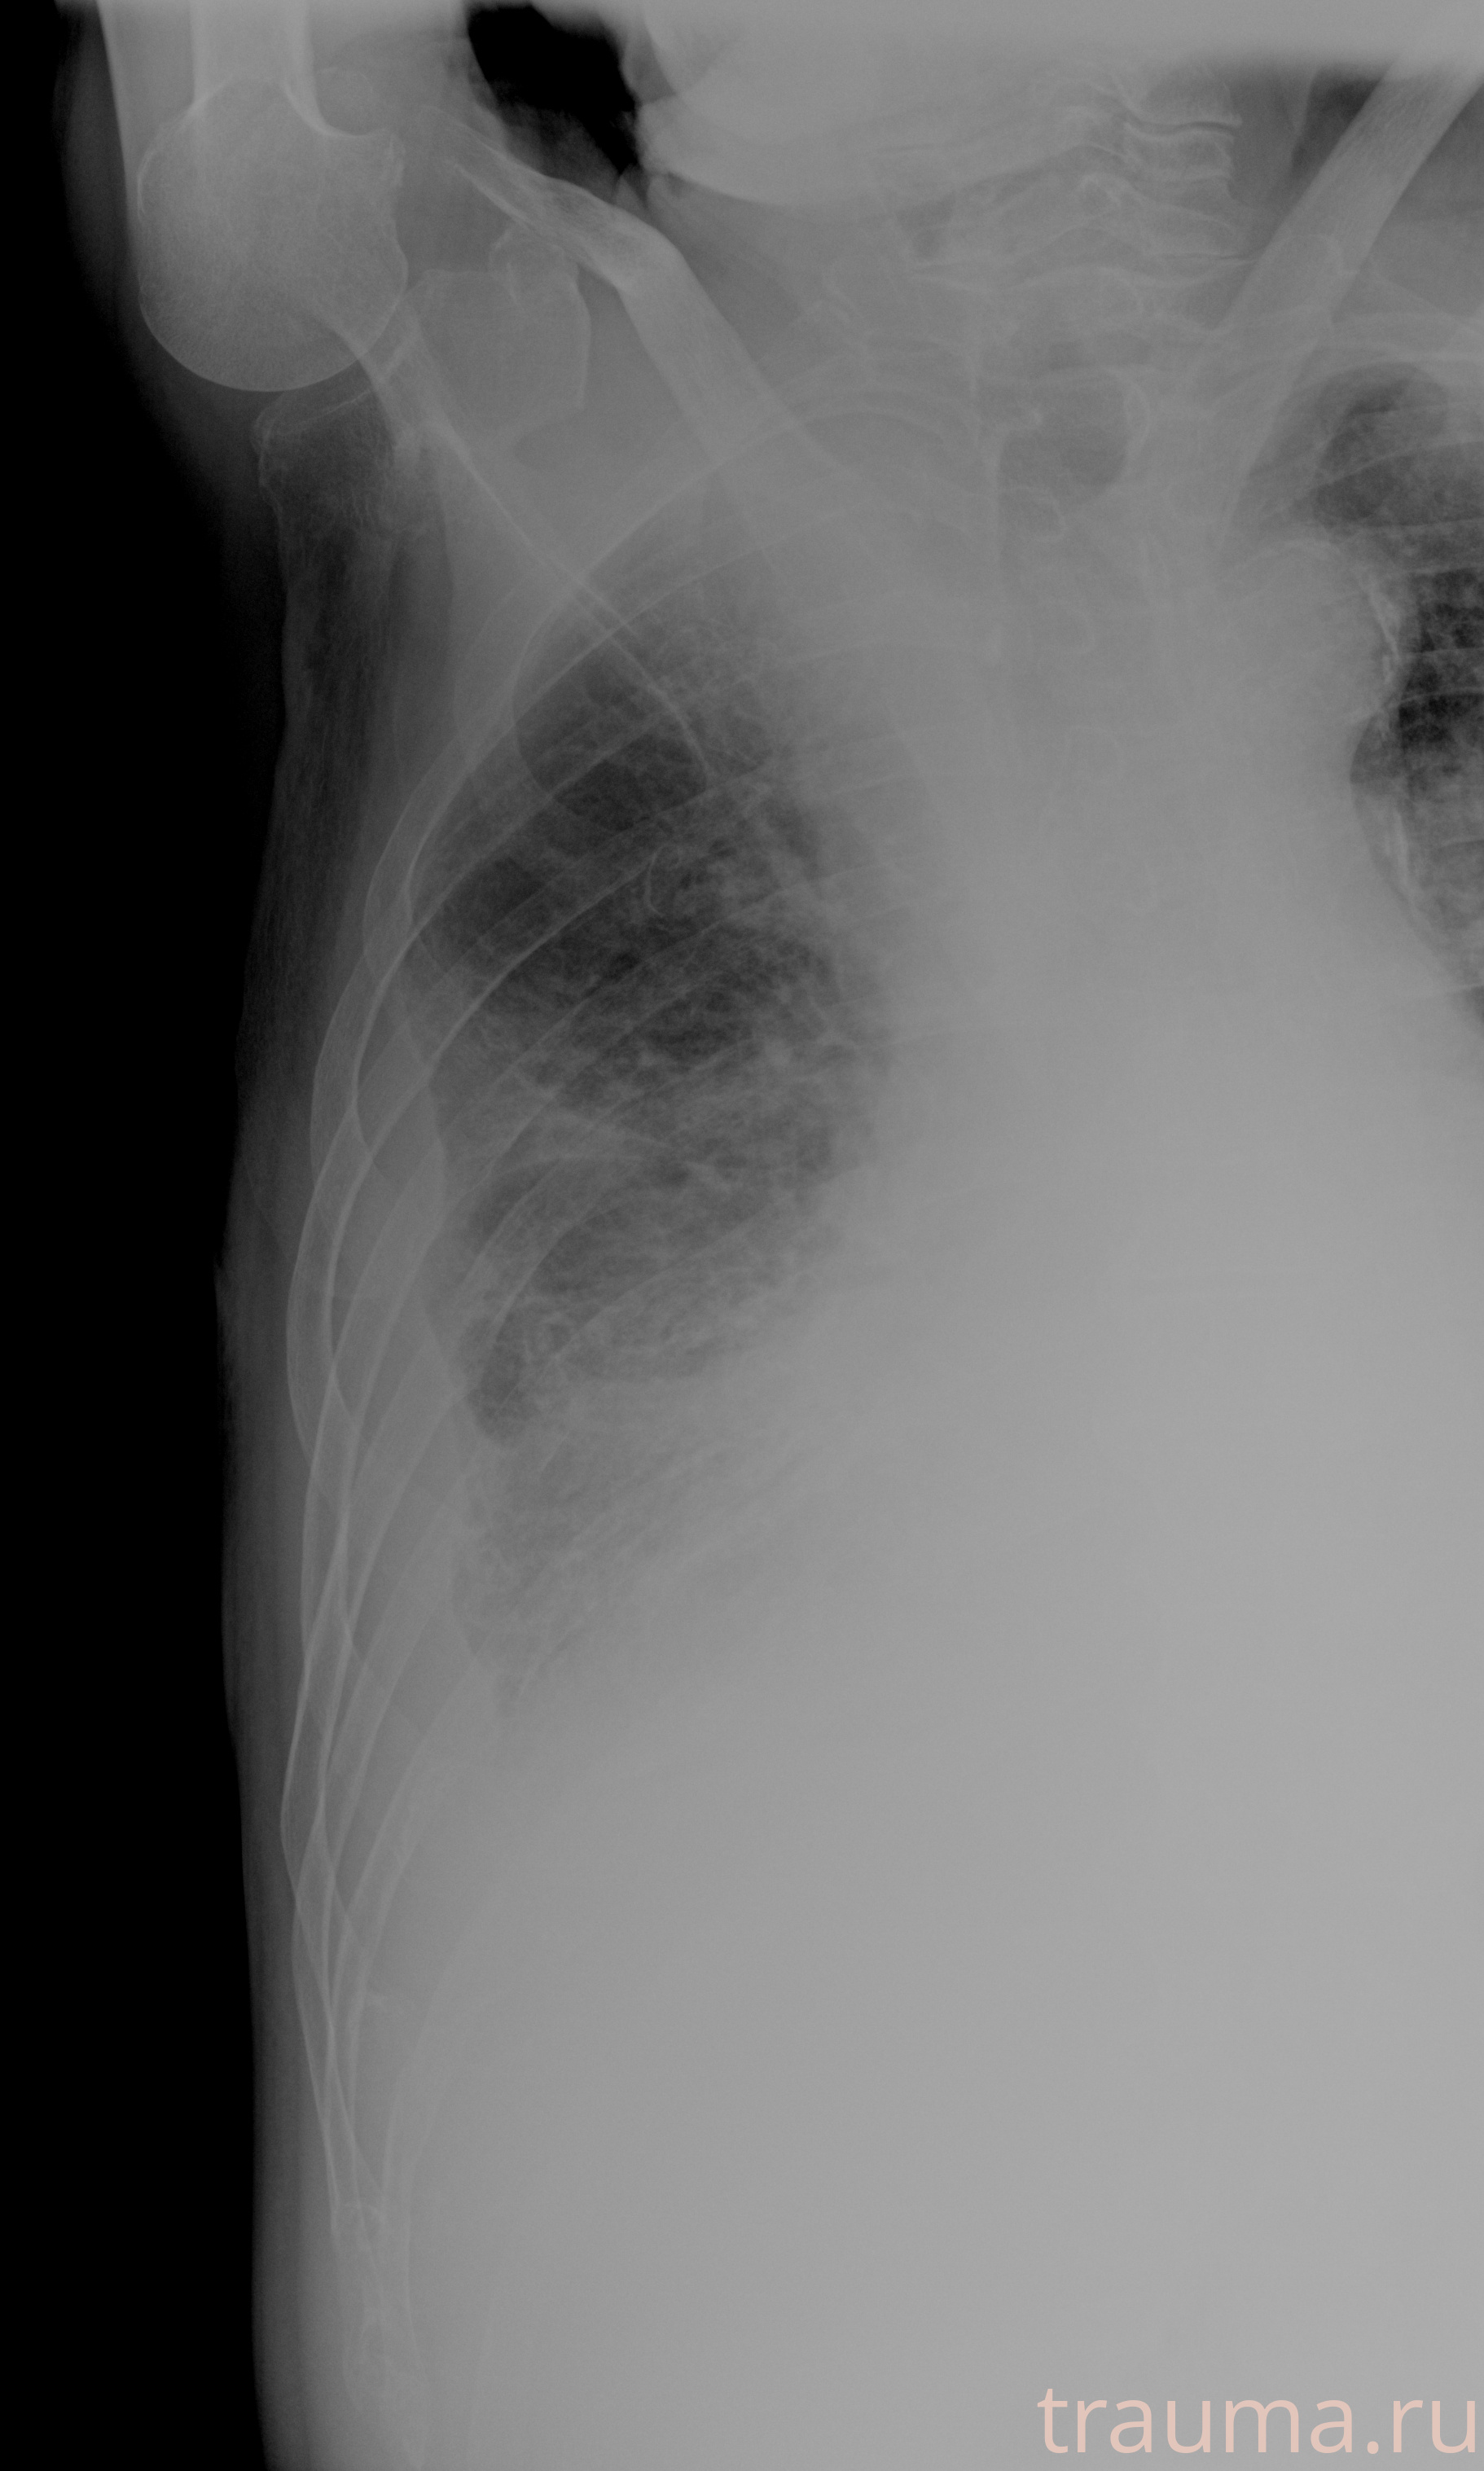

Рентген на дому: по вашему адресу приезжает врач-рентгенолог, травматолог-ортопед с мобильным рентгеновским аппаратом, проводит диагностику травмы или заболевания, делает необходимые рентгенограммы, дает рекомендации по дальнейшему лечению. Получить качественные снимки в домашних условиях возможно благодаря уникальной методике, разработанной МосРентген Центром для института  Склифосовского

при переломе шейки бедра и пневмонии от компании МосРентген Центр - партнера Института имени Склифосовского